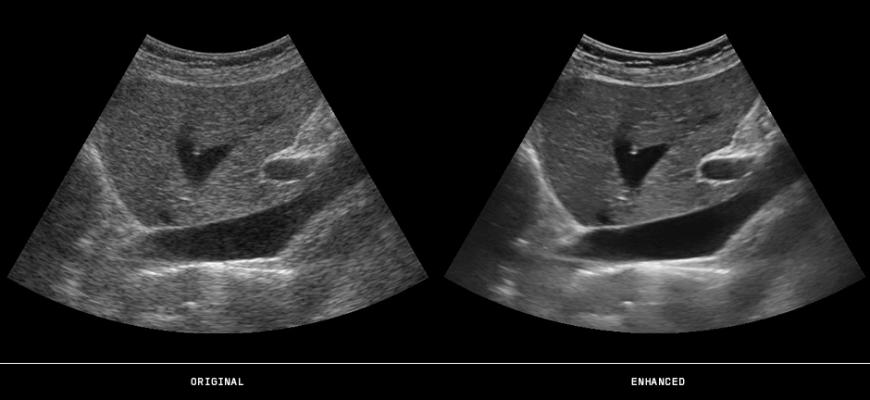

October 7, 2016 — ContextVision’s US PLUSView 2.0 technology for 2-D ultrasound image enhancement has been extended for implementation on the iOS platform. This allows for implementation on handheld mobile phone-based ultrasound devices, addressing a growing market for patient care.

US PLUSView provide features such as:

- DFE (directed focused enhancement) of anatomical features

- Advanced motion compensated temporal filter

- Near and far field filtering

- Optimized contrast

- Superior edge enhancement

- Intelligent speckle reduction